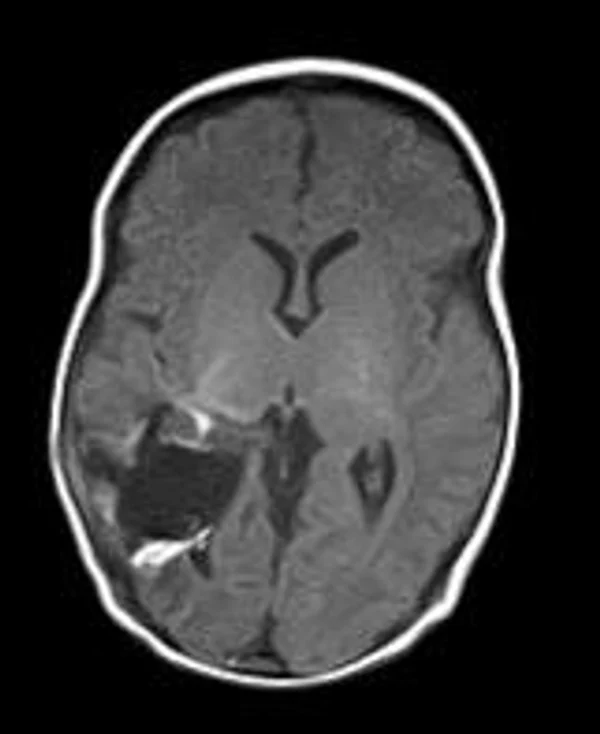

В качестве примера приведены 2 случая хирургического лечения новорожденных с врожденными опухолями головного мозга и позвоночного канала. У новорожденной девочки опухоль (хориодпапиллома) располагалась в области треугольника правого бокового желудочка (рис. 28 а, б). В возрасте 2-х недель жизни опухоль удалена. По данным МРТ головы с внутривенным введением контрастного препарата выполненной через 2 дня после операции опухоль удалена тотально (рис. 28 в). Послеоперационных осложнений не наблюдалось. У второго пациента 2-х нед. жизни врождённая опухоль (нейробластома) располагалась в позвоночном канале на уровне Th10-L3 позвонков (рис. 29 а) и распространялась в забрюшинное пространство. Клиническая картина заболевания складывалась из нижнего вялого парапареза и нарушения функции тазовых органов. Во время операции остистые отростки Th 11-L3 позвонков рассечены по средней линии. Дужки 6 данных позвонков надломлены и разведены в стороны. Опухоль располагалась экстрадурально, отделена от дорзальной поверхности дурального мешка и корешков спинно-мозговых нервов, после чего полностью удалена из позвоночного канала. Половинки дужек позвонков сведены к средней линии и сшиты между собой. Опухолевый узел в забрюшинном пространстве через 2 нед. удален онкологами. Через год после операции по данным МРТ рецидива опухоли нет (рис. 29 б). При спондилографии дефектов задней стенки и деформаций позвоночника не выявлено (рис. 29 в). Мальчик ходит, мочу и кал удерживает.